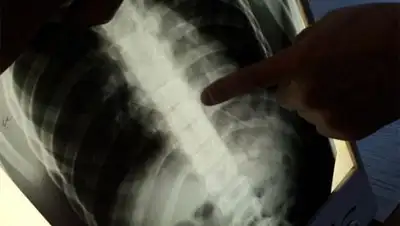

- Все что касается обстоятельств получения травмы, мы знаем их только со слов ребенка. Хотя описанные события  вызывают  у нас вопросы, но это уже не наше дело, а прерогатива полиции, – говорит заведующий  отделением общехирургической патологии детской больницы Аман Нажметдинов. – Ребенок рассказал, что у него  в рюкзаке были карандаши без пенала. И вероятно, когда он падал на спину, один из них вошел в подлопаточную область. Районный хирург сделал рентгенограмму грудной клетки так, как он жаловался на боль в груди. На рентгене хирург заметил слабовыраженную тень длиной сантиметров 8.

- Мы также произвели рентгенограмму. На двух проекциях была также замечена тень по направлению к перикарду, то есть к сердцу. Если бы инородное тело получило немного другое направление, оно могло бы войти  в сердце, – рассказывает хирург.